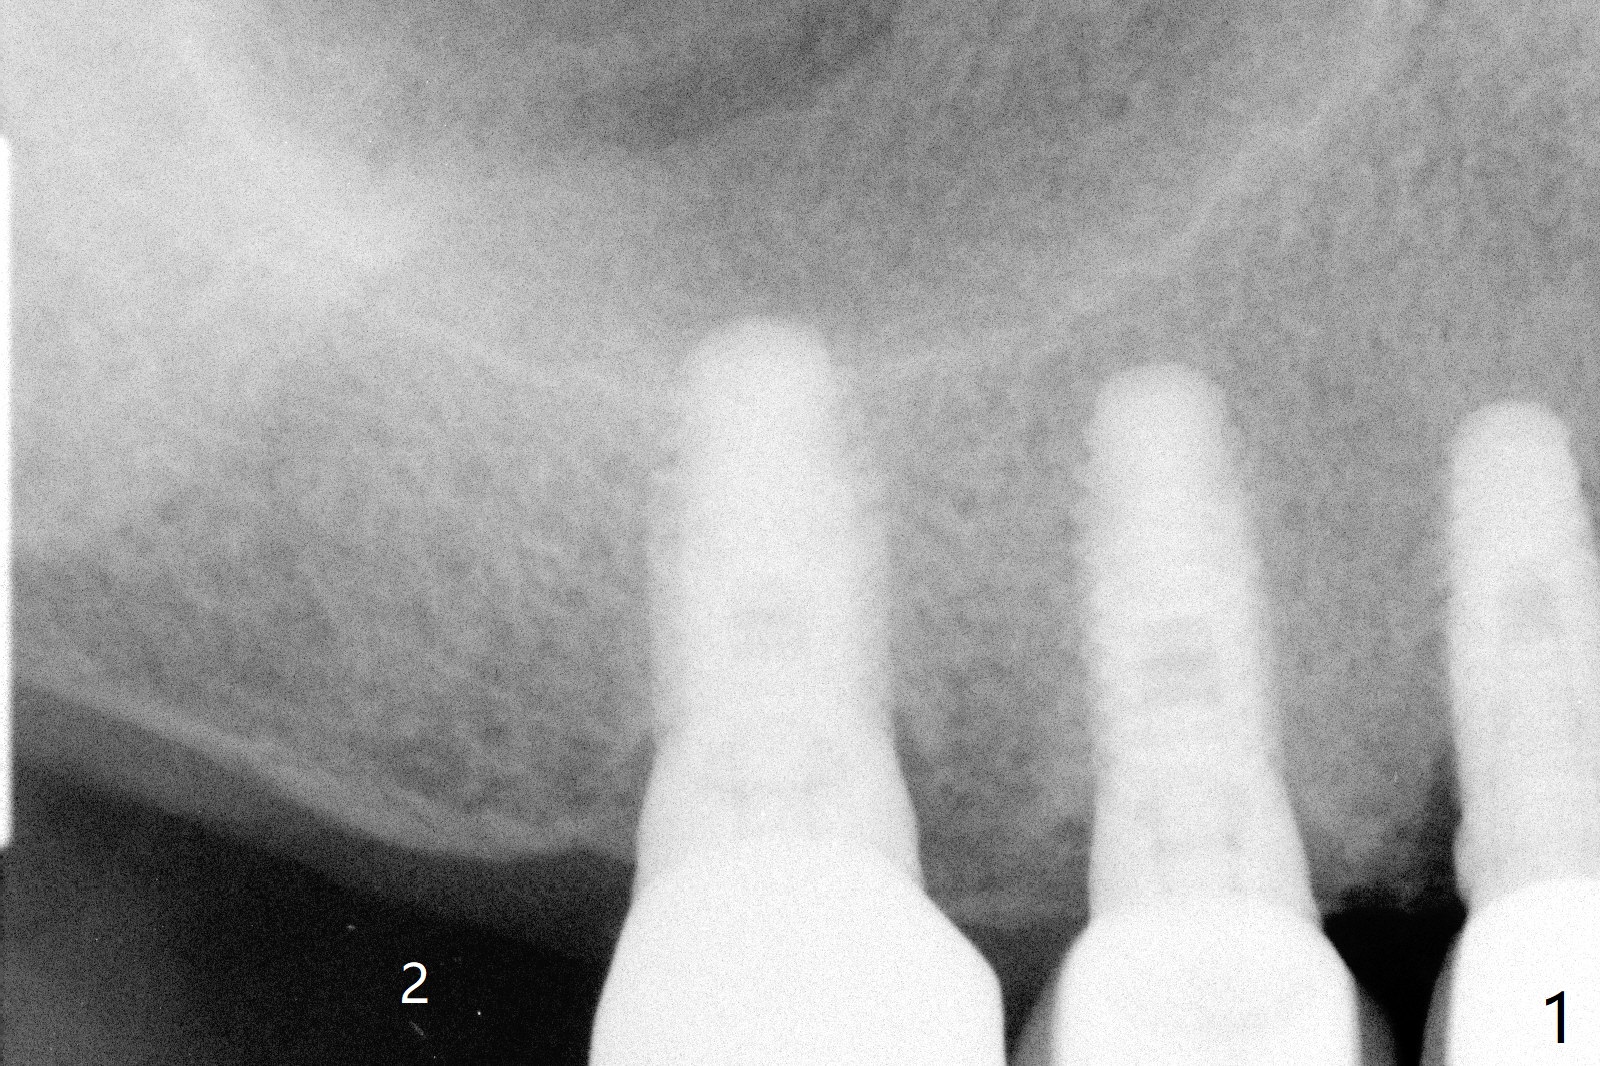

A 70-year-old man agrees to have an implant to be placed at the site of #2 (Fig.1). A 6x5.7 mm implant is placed ~ 3 mm subcrestal and covered by autogenous bone coronally (Fig.2 *). The implant plateau is surrounded by the bone 5 years 4 months post cementation (Fig.3 arrowheads). The implant fins are fully protected. Equally amazing is no history of screw loosening in spite of off-center placement of the implant.